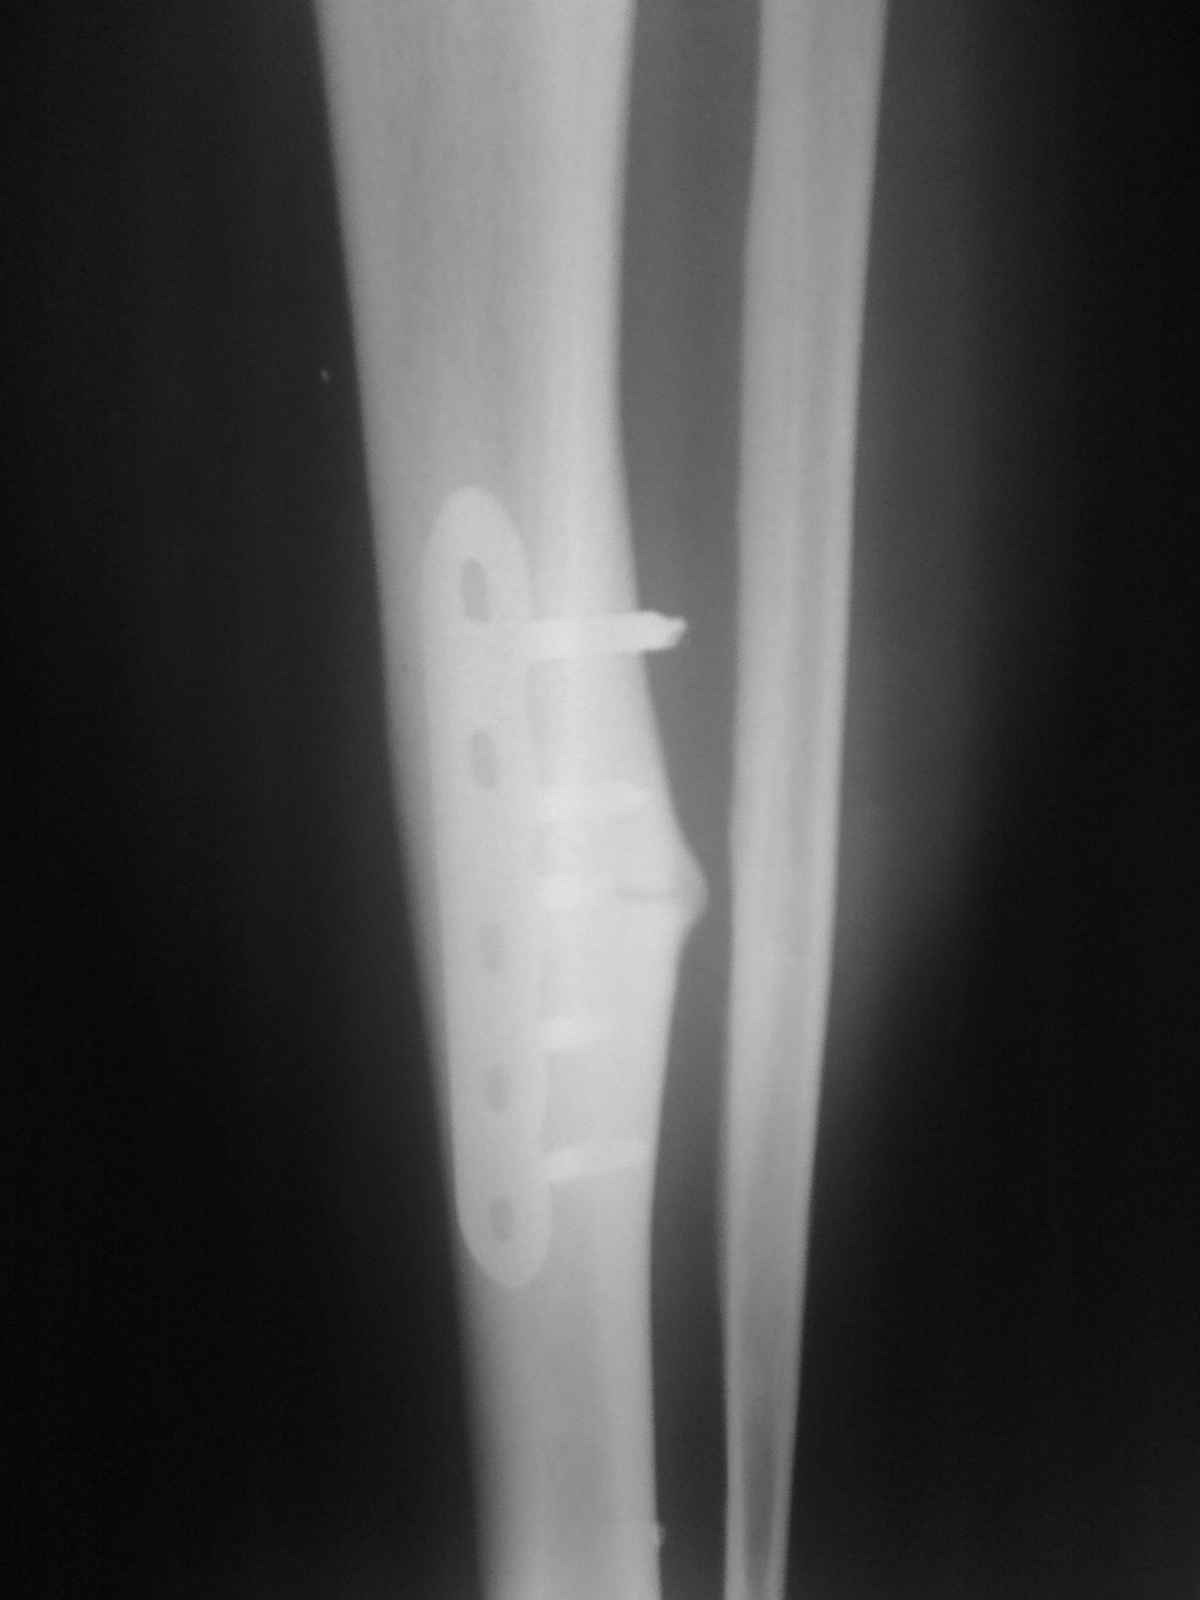

[Ortho] Патологический перелом большеберцовой кости.

Р-гр